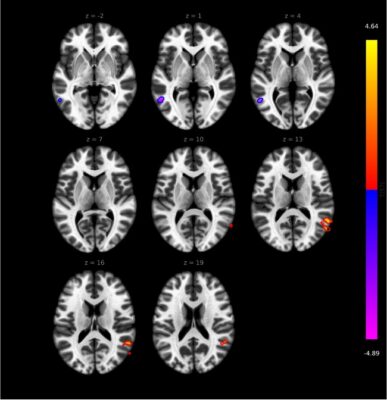

A kutatásban 30 nehezen kezelhető, 20 nem nehezen kezelhető páciens és 30 egészséges kontrollszemély vett részt. A vizsgálatok közt szerepelt egy átfogó klinikai állapotfelmérés, pszichológiai elemzés, funkcionális MR-vizsgálat, valamint transzkriptomikai (különböző szervekben, szövetekben sejttípusokban és különböző körülmények között a genomról átíródó RNS-molekulák nagy áteresztőképességű vizsgálata) és metabolomikai elemzések (specifikus, sejtszintű folyamatok által hátrahagyott „kémiai ujjlenyomatok” vizsgálata). A kutatás eredményeként sikerült kimutatni, hogy nehezen kezelhető RA-s betegeknél a gyulladásos aktivitás, valamint a krónikus fájdalom és az ezzel járó pszichés terhek a központi idegrendszert is érintik – foglalta össze dr. Gunkl-Tóth Lilla. A gyulladás, a fájdalom és a pszichológiai tényezők közötti kapcsolat feltárása és a jelátviteli útvonalak azonosítása pedig segítheti a kezelések jövőbeli fejlesztését – hangsúlyozta a kutató.

Dr. Nagy György hozzátette, hogy ez a felismerés alapvető személetváltást hozhat, mivel eddig az RA-t elsősorban ízületi betegségként kezelték. Mint mondta, a mostani eredmény nagy előrelépés: a kutatás arra próbált rávilágítani, hogy az agyban is van egy ujjlenyomata a betegségnek, ami lényeges változást hozhat a terápiában. Az igazgató kitért rá, hogy a Reumatológiai és Immunológiai Klinikán jelenleg is egyedi módon kezelik az RA-s betegeket: a gyógyszeres terápia és szteroidok mellett jelentős szerepet kapnak a nem gyógyszeres kezelési lehetőségek is.

A kutatásról és annak eredményeiről szóló publikáció még folyamatban van, dr. Gunkl-Tóth Lilla már több konferencián bemutatta munkájukat. Októberben Chicagóban az American College of Rheumatology (ACR) Convergence konferencián prezentálja „Multimodal Analysis Revealed Altered Brain Connectivity Patterns and Neuroinflammatory Processes in the Background of Difficult-To-Treat Rheumatoid Arthritis” („Megváltozott agyi kapcsolódási mintákat és neurológiai gyulladásos folyamatokat tárt fel egy multimodális elemzés a nehezen kezelhető reumatoid artritisz hátterében”) című előadását. Ez a konferencia az egyik legjelentősebb éves tudományos rendezvény a reumatológia területén, ahol reumatológiával foglalkozó magyar kutató még sosem kapott korábban lehetőséget, hogy bemutasson egy Magyarországon, teljesen hazai forrásokból végzett munkát. A szervezők már az absztrakt alapján odaítélték dr. Gunkl-Tóth Lillának az Emerging Investigator Excellence Award díjat, amelyet személyesen a konferencián vehet át, és amit digitális jelvény formájában fel is tüntethet majd az előadása során.